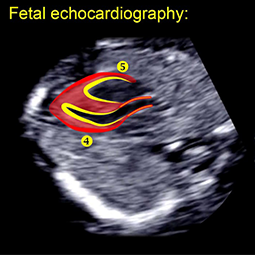

اکوی قلب جنین؛ این آزمایش معمولاً توسط یک متخصص سونوگرافی آموزش دیده انجام می شود و تصاویر توسط یک متخصص قلب کودکان که در بیماری قلبی مادرزادی جنین تخصص دارد، تفسیر می شود. برخی از متخصصان طب مادر و جنین (پریناتولوژیست) نیز اکوکاردیوگرام را انجام می دهند. ارزیابی محدودی از قلب جنین در طول اسکن منظم زنان و زایمان امکان پذیر است و برای زنان در معرض خطر پایین مناسب است. با این حال، زنانی که دارای یکی از عوامل خطر ذکر شده در بالا هستند، باید یک اکوکاردیوگرام دقیق جنین را توسط پزشکی که به طور ویژه در ارزیابی قلب جنین آموزش دیده است، انجام دهند.

اکوکاردیوگرافی جنین ارزیابی اولتراسونیک سیستم قلبی عروقی جنین انسان است. سونوگرافی عمومی زنان و زایمان قبل از زایمان به بخشی استاندارد از مراقبت های بارداری تبدیل شده است و معمولاً برای تعیین سن، اندازه، جنسیت، یا سلامت جنین و برای تشخیص ناهنجاری های مادرزادی استفاده می شود. انواع اختلالات مادر یا جنین ممکن است منجر به ناهنجاری در سیستم قلبی عروقی جنین به درجه ای شود که نیاز به ارزیابی در سطحی بالاتر و فراتر از آن دارد که با سونوگرافی استاندارد قبل از زایمان قابل دستیابی است. در این شرایط باید اکوکاردیوگرام جنین انجام شود.

اکوکاردیوگرافی جنین یک روش تشخیصی است که در ارزیابی قلب نوزاد در رحم مادر به روش سونوگرافی استفاده می شود. در این روش اطلاعاتی در مورد وضعیت ساختمانی و عملکرد قلب از طریق امواج صوتی اولتراسونیک به دست می آید.

این معاینه قلب نوزاد داخل رحمی است که از طریق سونوگرافی انجام می شود که از امواج صوتی استفاده می کند و تصاویری از قلب جنین تولید می کند. بنابراین امکان ارزیابی آناتومی و عملکرد آن فراهم می شود. باید از دستگاه سونوگرافی پیشرفته که دارای عملکرد داپلر رنگی است استفاده شود.